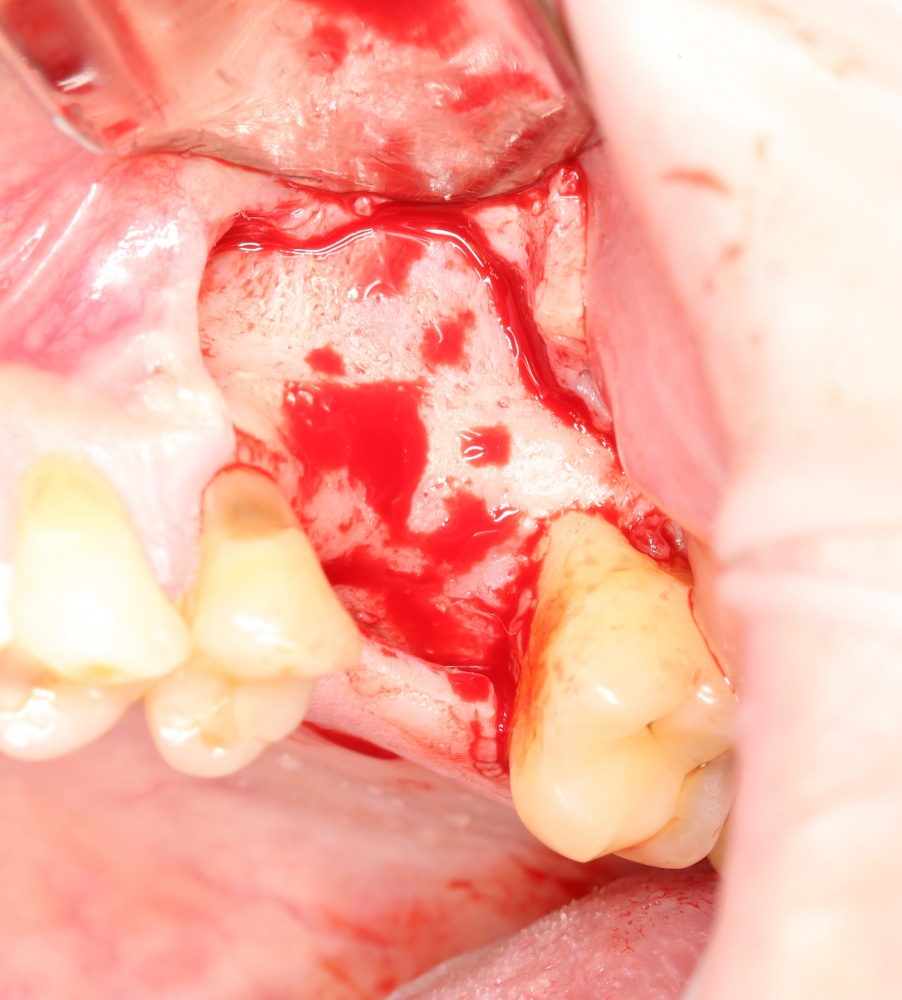

Возвращаемся к основной операционной области. Еще раз посмотрим на альвеолярный гребень, поофигеваем от его ширины и моих грандиозных планов:

На этом месте мне следует дать некоторые пояснения.

Если ты читал мои предыдущие публикации, посвященные остеопластике, то наверняка знаешь, что костное ложе перед фиксацией графта (любого графта) требует некоторой подготовки. В основном она заключается в полном или частичном удалении кортикального слоя и, применительно к АТККФ — адаптации не только блока под ложе, но и ложа под пересаживаемый костный блок. Подробности здесь>>

Ежу понятно, что к необходимости этих манипуляций мы пришли не сразу. А тогда был 2013 год… и у меня были мысли, что подготовка костного ложа нужна не всегда и не всем. Здесь я понадеялся на размер костного дефекта и большую площадь контакта между костным аутотрансплантатом и принимающим ложем. Конечно, сейчас я сделал бы немного по-другому.

Я зафиксировал костный блок практически без адаптации на несколько винтов. Обрати внимание, что винты находятся в зоне, где не планируется установка имплантатов. Фиксация должна быть надежной, поскольку мне еще предстояла подготовка лунок для имплантатов. Трех винтов для этого вполне достаточно.

Дальнейшая адаптация костного блока свелась к сглаживанию острых краев. После чего я приступил к подготовке лунок и установке имплантатов.

Установка имплантатов.

Напомню, что для этой работы я выбрал субкрестальные имплантаты Ankylos C/X. Они прекрасно сочетаются с любым методом остеопластики.

Глянем на то, что получилось:

Осталось адаптировать костный блок (убрать острые края), проверить его фиксацию и, при необходимости, добавить винты. Десятисекундное дело.